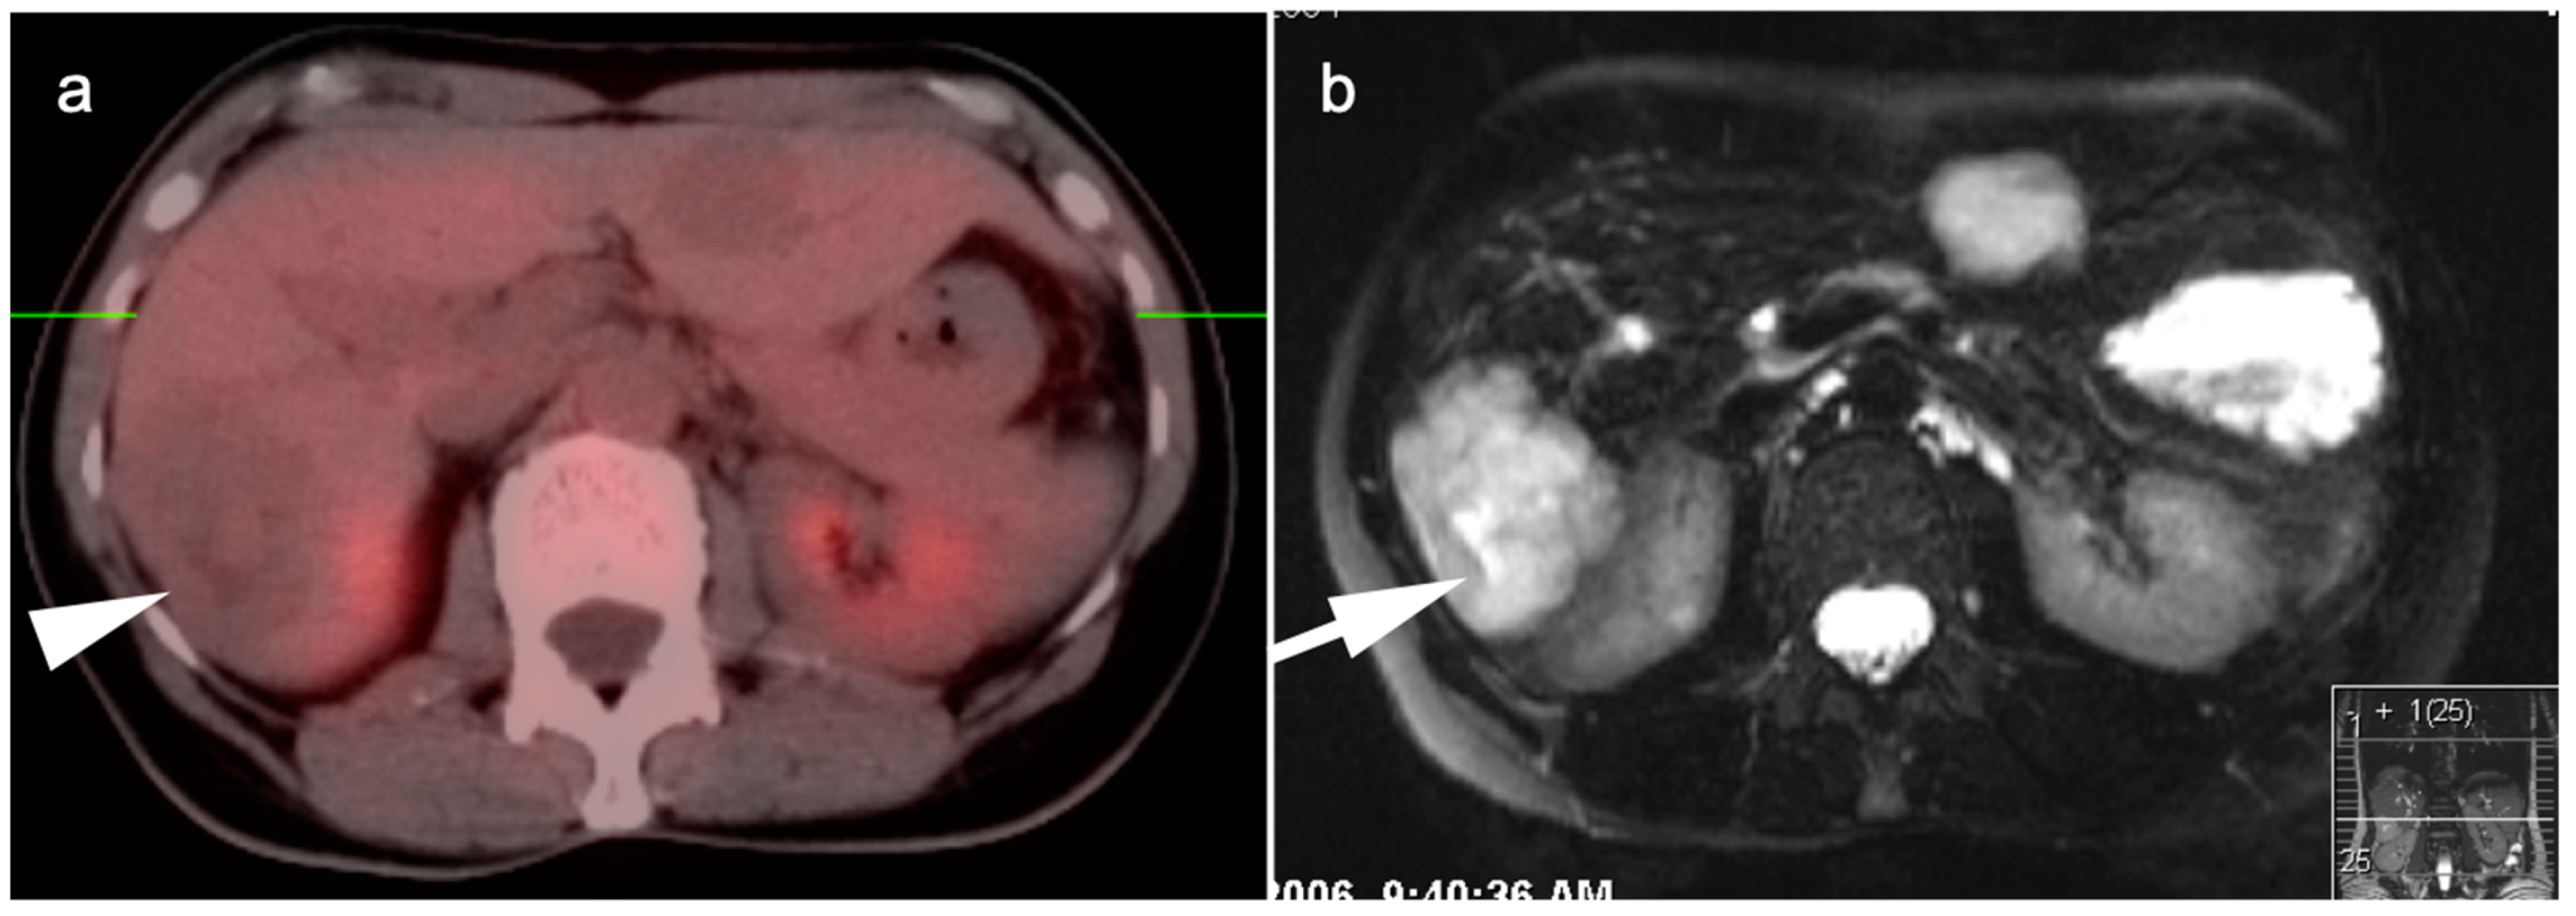

- Dinnes, J.; Bancos, I.; Ferrante Di Ruffano, L.; Chortis, V.; Davenport, C.; Bayliss, S.; Sahdev, A.; Guest, P.; Fassnacht, M.; Deeks, J.; et al. Management of endocrine disease: Imaging for the diagnosis of malignancy in incidentally discovered adrenal masses: A systematic review and meta-analysis. Eur. J. Endocrinol. 2016, 175, R51–R64. [Google Scholar] [CrossRef] [PubMed]

- Okada, M.; Shimono, T.; Komeya, Y.; Ando, R.; Kagawa, Y.; Katsube, T.; Kuwabara, M.; Yagyu, Y.; Kumano, S.; Imaoka, I.; et al. Adrenal masses: The value of additional fluorodeoxyglucose-positron emission tomography/computed tomography (FDG-PET/CT) in differentiating between benign and malignant lesions. Ann. Nucl. Med. 2009, 23, 349–354. [Google Scholar] [CrossRef]

- Vos, E.L.; Grewal, R.K.; Russo, A.E.; Reidy-Lagunes, D.; Untch, B.R.; Gavane, S.C.; Boucai, L.; Geer, E.; Gopalan, A.; Chou, J.F.; et al. Predicting malignancy in patients with adrenal tumors using 18F-FDG-PET/CT SUVmax. J. Surg. Oncol. 2020, 122, 1821–1826. [Google Scholar] [CrossRef]

- Kunikowska, J.; Matyskiel, R.; Toutounchi, S.; Grabowska-Derlatka, L.; Koperski, L.; Krolicki, L. What parameters from 18F-FDG PET/CT are useful in evaluation of adrenal lesions? Eur. J. Nucl. Med. Mol. Imaging 2014, 41, 2273–2280. [Google Scholar] [CrossRef]

- Dong, A.; Cui, Y.; Wang, Y.; Zuo, C.; Bai, Y. 18F-FDG PET/CT of Adrenal Lesions. AJR Am. J. Roentgenol. 2014, 203, 245–252. [Google Scholar] [CrossRef]